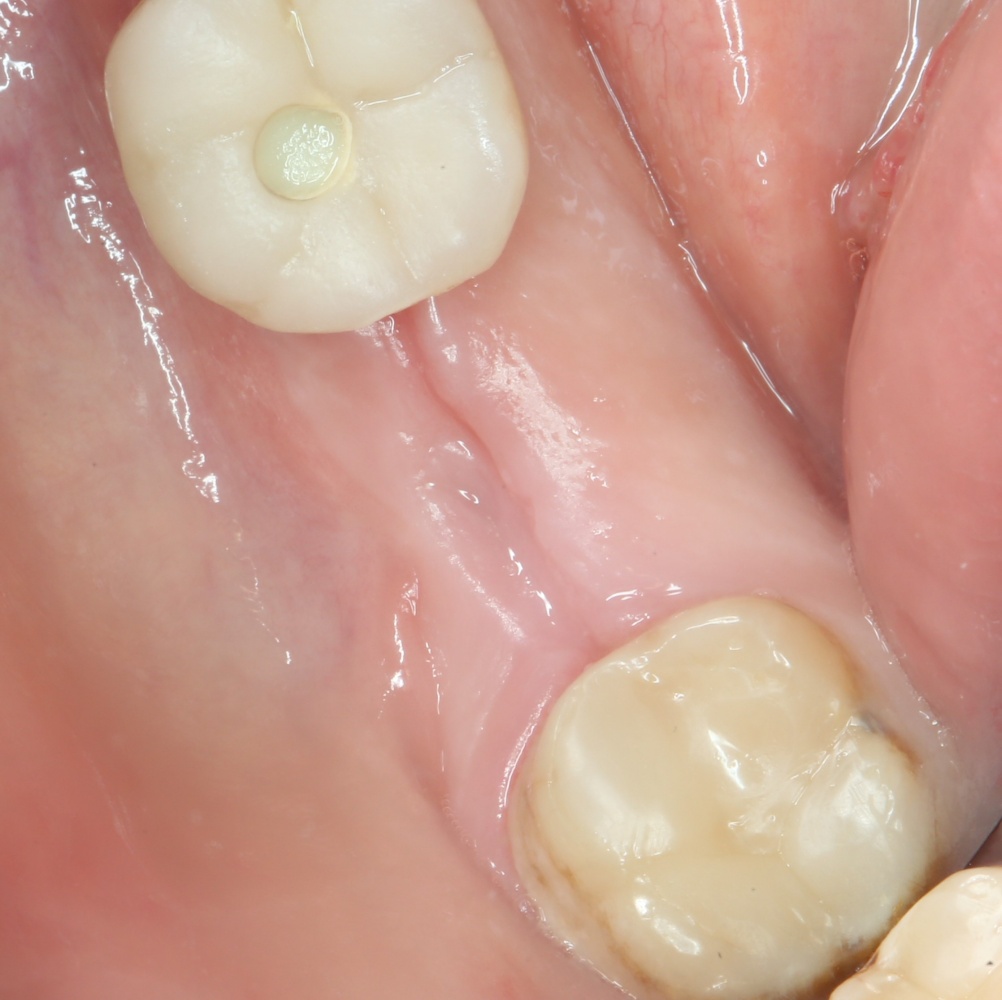

Рекомендации по установке имплантов. Для всех. Часть II.